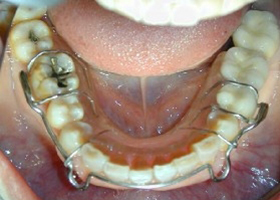

4.使用活動式矯正裝置矯正中(矯正方式因人而異)。

proimages/case/cosmetic/pic_case-025.jpg